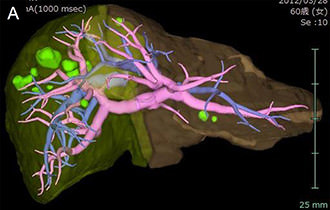

図2 VINCENTによるシミュレーション画像

肝臓や脈管の3次元的な描出が可能です。

さらに肝切除予定領域が緑色と黄色で示されています (B)。

• シミュレーション画像:肝切除予定領域が緑色と黄色で示されている